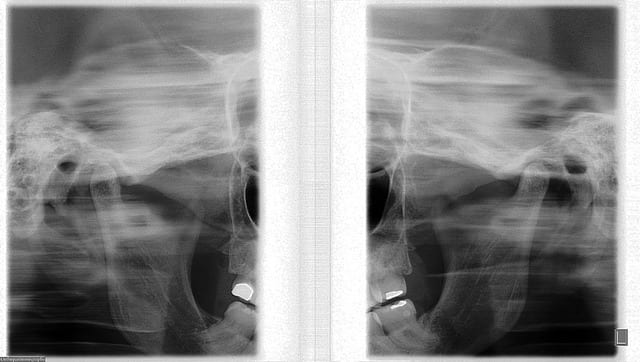

l'ATM. droit à l'air bien, mais le gauche semble encore imparfait. tu compte faire quoi?

Tu vas encore dire qu'il me manque les bases, mais ...

Tu peux m'expiquer les différences, parce que cela ne me saute pas au yeux..

Toujours pas de réponse à mes questions assez simples : tu nous montres une pano fièrement en nous disant " je vous laisse juge... ".

J'avoue mon incompétence : je ne vois rien de différent par rapport au début de traitement. Peux tu m'éclairer ?

Pour la radio, je vais finir par croire que, toi non plus, tu ne vois pas de différence, puisque tu bottes en touche en m'envoyant sympathiquement chez le radiologue. il devrait pour être possible de rendre le montage que j'ai fais, d'ajouter des petites flèches et de dire " et bien, tu vois, c'est comme ça, c'est mieux que la, etc .

si d'autre eugénolien savent lire une radio, ils sont également les bienvenus pour me faire cette explication. ou alors, on envoi tout le monde chez le radiologue :)

Quand aux radios, on ne voit effectivement aucune différence entre avant et après. Si jeff n'avait pas fait l'effort de rechercher les premières, on aurait tous été piégés.